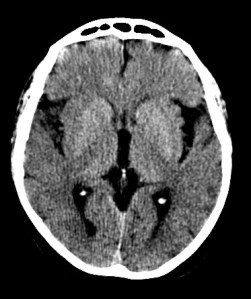

CASO 1:

Paciente con disminución de la conciencia y alteraciones de habla. El cuadro parece progresivo. Dislipemia y Diabetes Mellitus tipo II como antecedentes personales.

ASPECTS: Afectación Ribete Insular + Lenticular + Territorio M2 = 10 – 3 = 7 puntos.